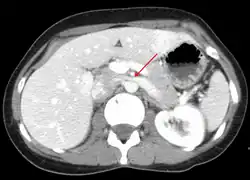

The nutcracker syndrome results from compression of the left renal vein between the aorta and the superior mesenteric artery.

Nutcracker syndrome is diagnosed through imaging such as doppler ultrasound (DUS), computed tomography (CT), magnetic resonance imaging (MRI), and venography.[15] The selection of the imaging modality is a step-wise process. DUS is the initial choice after clinical suspicion based on symptoms. CT and MRI are used to follow up afterwards, and if further conrfirmation is necessary, venography is used to confirm.[15]

CT and MRI

CT and MRI can be used afterward to confirm compression by the AA and SMA with comprehensive measurements of the abdominal vasculature. A "beak sign" can often be seen in CT scans due to the LRV compression. However, CT and MRI cannot demonstrate the flow within the compressed vein. These two modalities can be used to confirm other evidence for NCS such as back-up of blood flow into the ovarian veins.[14][9]